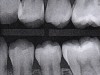

Interproximal insertion of SDF is demonstrated in different patients in Figure 3 through Figure 11. Various diameters and brands of soft dental picks may be used depending on the closeness of the proximal surfaces and ease of insertion; for example, some picks are designed for use in wider spaces between teeth. This protocol also offers versatility. Figure 3, for example, shows the simultaneous use of three thin soft dental picks to saturate proximal surfaces with SDF in a teenaged patient; the treated regions were subsequently covered with fluoride varnish (Figure 4). This patient was initially treated in April 2019 (Figure 5), with an identical re-application 3 months later. As shown in Figure 6, the December 2019 bitewing film revealed good results with the possible exception of the contact regions of the maxillary first and second molars. New SDF application was completed in the December appointment.

Fig 3. Three thin soft dental picks were used simultaneously for SDF proximal surface saturations in a teenaged patient (Fig 3). After 60 seconds, the treated regions were covered with 5% fluoride varnish (Fig 4). A comparison can be seen of pre-SDF-treatment bitewing films (Fig 5) and 8-month post-SDF bitewing films (Fig 6) for the patient shown in Fig 3 and Fig 4. Radiolucencies were similar or improved, except for contact of maxillary first and second molars.

Fig 5. Three thin soft dental picks were used simultaneously for SDF proximal surface saturations in a teenaged patient (Fig 3). After 60 seconds, the treated regions were covered with 5% fluoride varnish (Fig 4). A comparison can be seen of pre-SDF-treatment bitewing films (Fig 5) and 8-month post-SDF bitewing films (Fig 6) for the patient shown in Fig 3 and Fig 4. Radiolucencies were similar or improved, except for contact of maxillary first and second molars.

Fig 6. Three thin soft dental picks were used simultaneously for SDF proximal surface saturations in a teenaged patient (Fig 3). After 60 seconds, the treated regions were covered with 5% fluoride varnish (Fig 4). A comparison can be seen of pre-SDF-treatment bitewing films (Fig 5) and 8-month post-SDF bitewing films (Fig 6) for the patient shown in Fig 3 and Fig 4. Radiolucencies were similar or improved, except for contact of maxillary first and second molars.